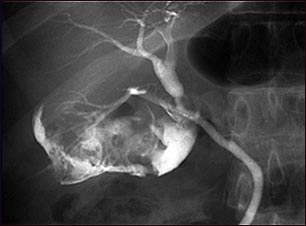

Colangiograma de una colecistitis

La colelitiasis se puede ver en un colangiograma. Se utiliza tinte radio opaco para mejorar la radiografía. En la vesícula biliar hay múltiples cálculos (PTCA).